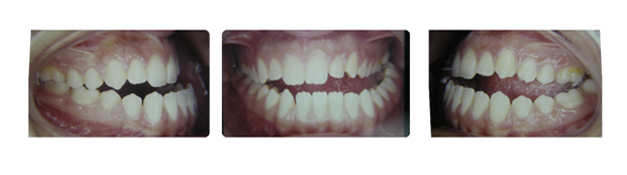

| دندانهای فک بالا و پایین دارای بی نظمی میباشند و با توجه به نبود فضا, بدون کشیدن دندان و توسط سیستم دیمون درمان میشوند: |

![]() |

| درمان با براکتهای دیمون نتیجه بخش است: |